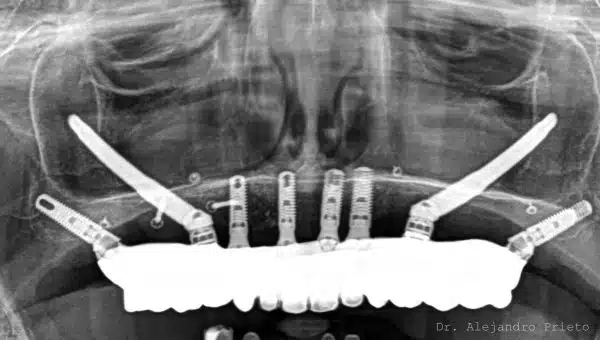

Los implantes pterigoideos son implantes dentales largos que se colocan en la apófisis pterigoidea , una zona ósea profunda y muy densa situada en la parte posterior del maxilar superior. Esta región ofrece una excelente estabilidad primaria , incluso en pacientes con gran pérdida ósea.

A diferencia de los implantes tradicionales, los implantes pterigoideos se colocan con una inclinación específica , anclándose en hueso de alta calidad y permitiendo la colocación de prótesis fijas sin necesidad de regeneración ósea previa.

Implantes pterigoideos y cigomáticos: ¿son lo mismo?

No. Aunque suelen mencionarse juntos, implants pterigoideos y cigomáticos no son lo mismo , aunque ambos se utilizan en pacientes sin hueso.

Implantes pterigoideos : se anclan en la zona pterigoidea del maxilar

Implantes cigomáticos : se anclan en el hueso cigomático (pómulo)

En muchos tratamientos avanzados se combinan estas técnicas implantológicas para lograr una rehabilitación completa y estable sin injertos óseos.

Implantes pterigoideos: antes y después

Los implantes pterigoideos permiten pasar de una situación de edentulismo o prótesis inestables a dientes fijos, incluso en pacientes con atrofia ósea severa.

A continuación se muestran casos reales de implantes pterigoideos antes y después, donde se aprecia la mejora funcional y estética.